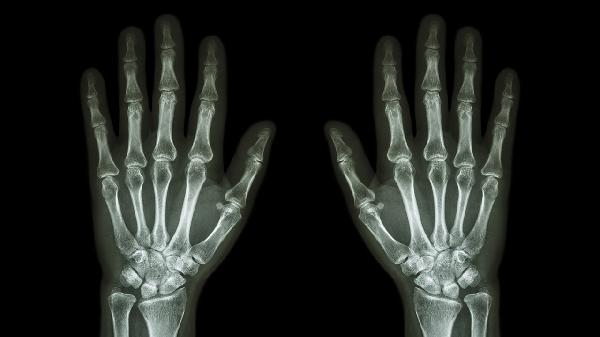

喝完酒后手指關(guān)節(jié)疼可通過調(diào)整飲食、熱敷緩解、避免飲酒、遵醫(yī)囑用藥、就醫(yī)檢查等方式改善。酒后關(guān)節(jié)疼痛可能與酒精代謝異常、痛風(fēng)發(fā)作、關(guān)節(jié)炎加重、尿酸水平升高、軟組織損傷等因素有關(guān)。

持續(xù)疼痛超過24小時或伴隨關(guān)節(jié)紅腫發(fā)熱時,需及時就診風(fēng)濕免疫科。通過血尿酸檢測、關(guān)節(jié)超聲等明確病因。痛風(fēng)性關(guān)節(jié)炎急性期可能需關(guān)節(jié)腔穿刺治療,骨關(guān)節(jié)炎患者需長期康復(fù)管理。飲酒后反復(fù)關(guān)節(jié)疼痛可能提示代謝性疾病,須完善肝腎功等系統(tǒng)檢查。